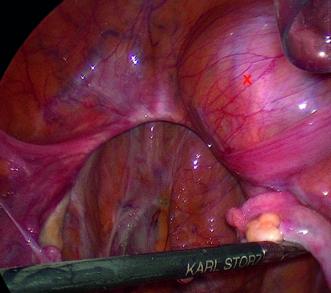

Während der Laparoskopie zeigte sich ein unauffälliger Situs bei Status nach Hysterektomie. Überraschenderweise waren auch die Ovarien makroskopisch unauffällig. In der rechten Fossa obturatoria hingegen fiel eine retroperitoneal gelegene Vorwölbung auf, welche bei Füllung der Harnblase gut von dieser abgrenzbar blieb (Abb. 2). Nach Durchführung einer Spülzytologie sowie der beidseitigen Adnexektomie folgte die Präparation dieser Raumforderung, welche in der Fossa obturatoria gelegen war. Der Tumor war mit dem N. obturatorius verwachsen (Abb. 3). Ein Ursprung aus dem Nerv schien nicht ausgeschlossen. Unter Erhaltung eines möglichst grossen Anteils des N. obturatorius wurde die Raumforderung vorsichtig in toto entfernt.